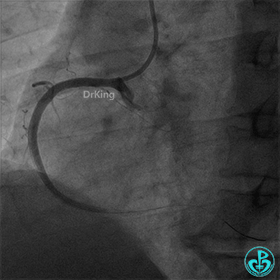

造影示右冠脉近段完全闭塞。

导丝通过,沿指引导管冠脉内注射用重组人TNK组织型纤溶酶原激活剂8mg,球囊扩张后,出现再灌注心律失常,“让子弹飞一会”,等待,未造影,5分钟后造影示右冠脉中段可见大量血栓,前向血流TIMI 2级。

冠脉血栓抽吸导管反复抽吸,未抽出典型血栓。

血栓移位至后三叉,冠脉血栓抽吸导管再次反复抽吸无果,送刺破球囊至RCA病变处再次冠脉内注射重组人TNK组织型纤溶酶原激活剂8mg,等待10分钟后造影示后三叉的血栓完全消失,前向血流TIMI 3级。

右冠脉近段植入1枚4.0×24mm支架,后扩张后造影示前向血流TIMI 3级。